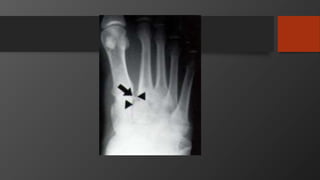

Fifth Metatarsal Fractures

• Common injury

• Divided into 3 zones

• Zone 2 is Jones fracture

• Zone 1 is Pseudojones fracture